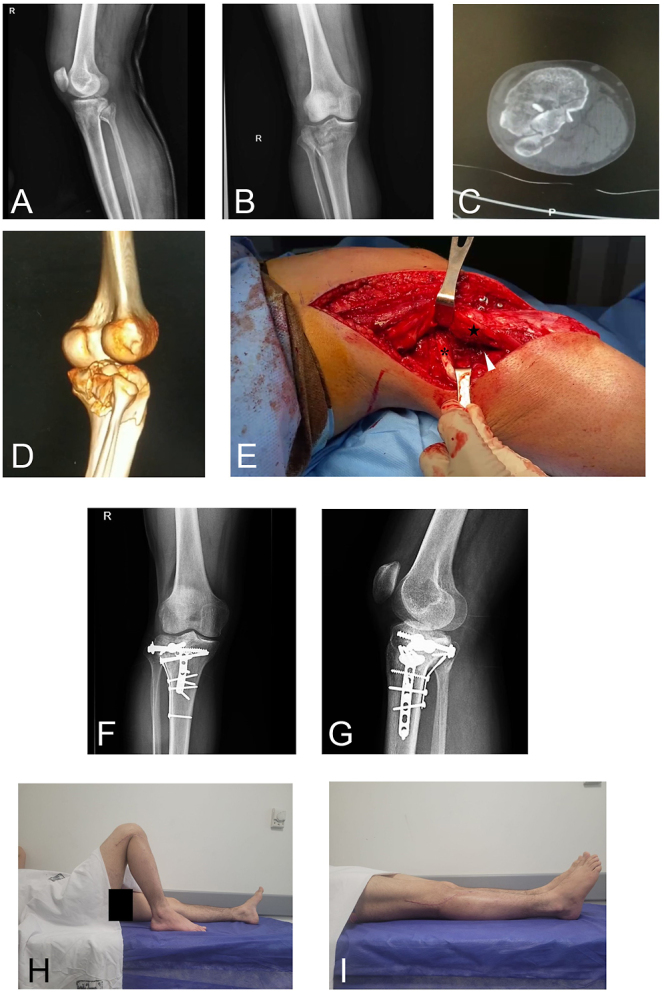

Abstract Image